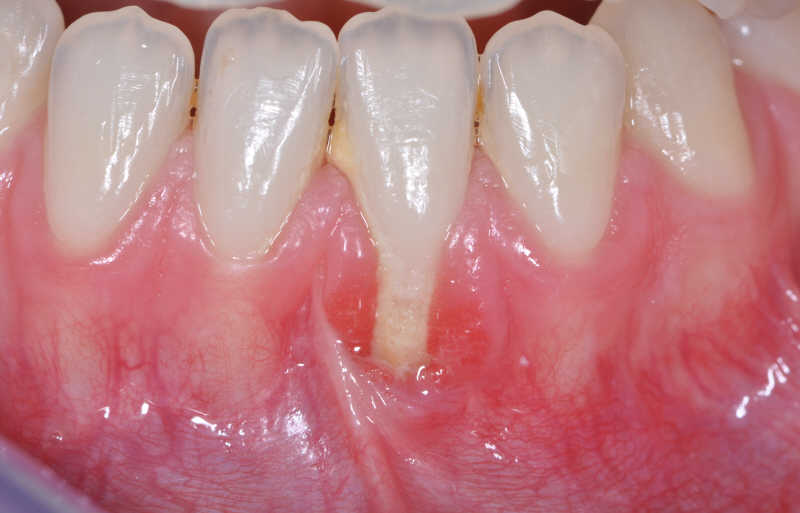

Forman parte del sistema de soporte de los dientes en los maxilares. Si la encía está sana, los dientes están perfectamente fijados, lo que garantiza una buena masticación y aíslan del organismo de agresiones del medio externo a través de la boca. La encía es un contribuyente del apoyo junto al hueso alveolar, y ligamento periodontal. El ligamento periodontal y el hueso alveolar insertan el diente en el organismo, y la encía es la barrera que protege el mismo de las agresiones tanto físicas como químicas, y bacterianas, que nos vienen del exterior.

La causa más frecuente de las encías inflamadas son las bacterias, en la boca existen más de trescientos tipos diferentes, muchas de ellas son potencialmente agresivas para el soporte. Las bacterias que habitan en la boca se esparcen sobre la superficie de los dientes, especialmente en el surco gingival, provocando la placa bacteriana. Cuando las bacterias crecen sobrepasando un cierto nivel, son capaces de producir lesiones en los tejidos periodontales. La gravedad de estas lesiones depende de la susceptibilidad individual que es una característica genéticamente determinada.